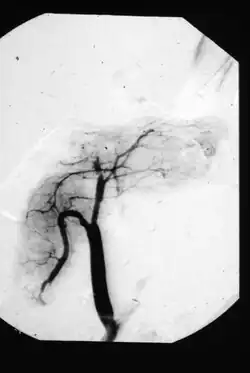

Wie kaum eine andere Organtransplantation war die Pankreastransplantation über lange Zeit von Modifikationen der chirurgischen Technik geprägt (siehe geschichtliche Entwicklung). Als Standardtechnik hat sich die Transplantation des gesamten Organs einschließlich eines etwa fünf bis zehn Zentimeter langen Segments des Duodenum (Zwölffingerdarm) (Pankreasduodenaltransplantation) etabliert. Das Duodenalsegment dient der Ableitung des Pankreassekrets über eine Enteroanastomose zum oberen Dünndarm (Jejunum) in der Dünndarmdrainagetechnik oder alternativ zur Harnblase (Blasendrainagetechnik). Die Blasendrainagetechnik (aktuell ca. 15 %) wurde allerdings zunehmend verlassen. Das Transplantat befindet sich meist intraperitoneal in heterotoper Position, also nicht an dem Ort der Bauchspeicheldrüse des Empfängers, welche dort verbleibt. Meist befindet sich das Transplantat im rechten Unterbauch. Die Arterien werden an die Arteria iliaca communis (Beckenhauptarterie) und die Transplantatvene (Vena portae) an die Vena cava inferior (untere Hohlvene) bzw. die Vena mesenterica superior (Darmvene) anastomosiert. Die venöse Anastomose zur Darmvene wird auch als portalvenöse Drainagetechnik bezeichnet. So können quasi physiologische Verhältnisse der Insulinwirkung erreicht werden.